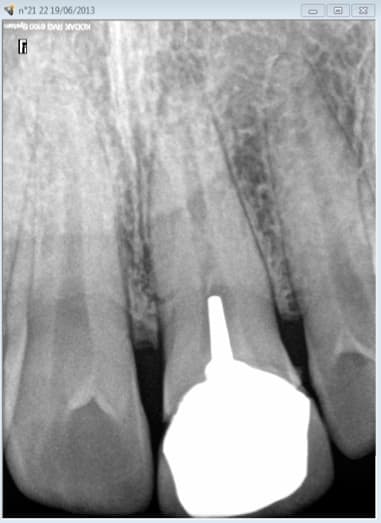

LRAR du jour.....

INDU

> LRAR du jour

> le RSI

> controle a posteriori bridge 45-46-47

> demande de radio 46 ( inter )

>

> je n'ai aucun cliché 46 depuis 2011

> résultat relance apres envoi de cette radio ancienne

> ai dit pas de radio => BAM les recommandations prévoient un cliché des piliers

> de bridge

> INDU

si t'as des clichés récents, avant traitement, de 45 et 47 (qui fort logiquement doivent démontrer l'absence de 46 si elles sont centrées), je vois pas le problème.

Ne pas prendre de cliché avant un traitement prothétique, quel qu'il soit, c'est prendre le risque de s'en manger une belle à postériori.

Rien que pour pouvoir justifier du caractère "non reconstituable de façon durable au moyen d'un matériau d'obturation classique inséré en phase plastique", ça mérite d'être fait.

Après, coter ou pas, c'est un autre problème.

Mais conserver !

Pose d'une couronne dentaire prothétique conjointe

...Couronne dentaire fixée dentoportée quand la dent ne peut être reconstituée de façon durable par une obturation.

La ou les radiographies dont la nécessité médicale est validée scientifiquement sont conservées dans le dossier du patient

Je ne connais pas de rapport HAS qui te dit qu'il faut prendre une radio avant chaque pose.

A mon sens il faut comprendre que tu ne fais de radio que si c'est justifié médicalement.

si tu estimes qu'il n'y a pas lieu de faire une radio, tu ne la fais pas. Et par conséquent tu n'es pas tenu de produire une radio qu'il n'était pas médicalement nécessaire de réaliser.

Et pour mémoire les radios à but administratif sont interdites puisque tu irradies ton patient inutilement, c'est inscrit dans la directive euratom.

En l'état Cyber tu devrais te rebiffer et leur demander sur quelles recommandations de bonne pratique ils se basent pour réclamer cet indu.

Le guide HAS sur les radios est assez complet, jette-y un œil tu n'y trouveras aucune référence à une radio obligatoire avant la pose d'une couronne ou un bridge

D'ailleurs on se demande pourquoi les radios sont obligatoires que pour les endos. -)

Pas de plaintes de patients de déposées ? de quoi je me mêle la sécu ? c'est pas comme si un CDC en avait quelque chose à faire de la qualité des soins ! -)

Tu fais une endo sous digue obturation à chaud nickel et ils viennent te faire chier sur un HBLD 040 de coté en plus d'une radio pré op. Tout ca pour récupérer 3,99 euros. -)

Si tu n'as pas de radios en cas de litige au tribunal ben tu perds, ca s'arrete là.

Traitement effectué avec radio pré op et post op, pas de plainte du patient ( qui adore son praticien et le remercie de l'avoir pris en urgence suite à un choc) , radios cotées, praticien pas emmerdé, tout baigne. -)